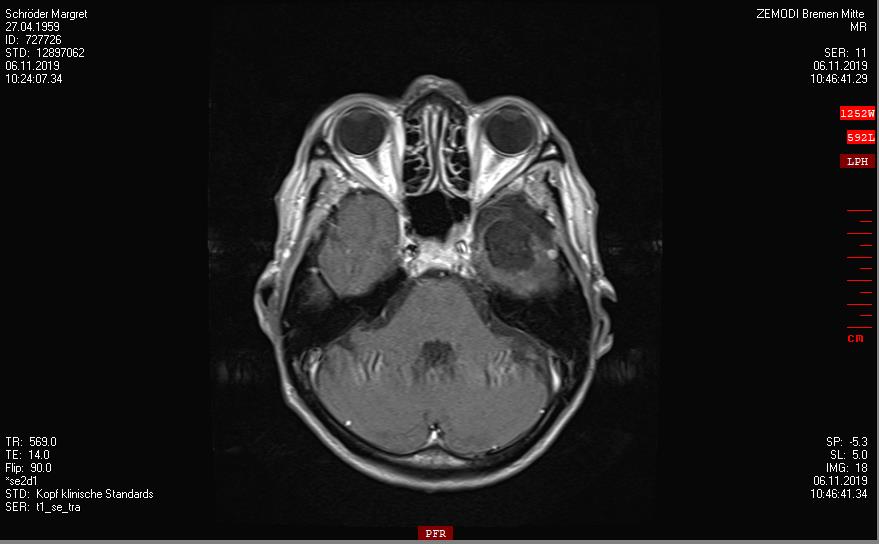

2019-2020

Ein Rezidiv wächst langsam

Die Tumorkonferenz vom Krankenhaus Bremen-Mitte rät zum Abwarten.

Der beratende Arzt dort, findet eine Bestrahlung im Gamma-Knife nicht falsch.